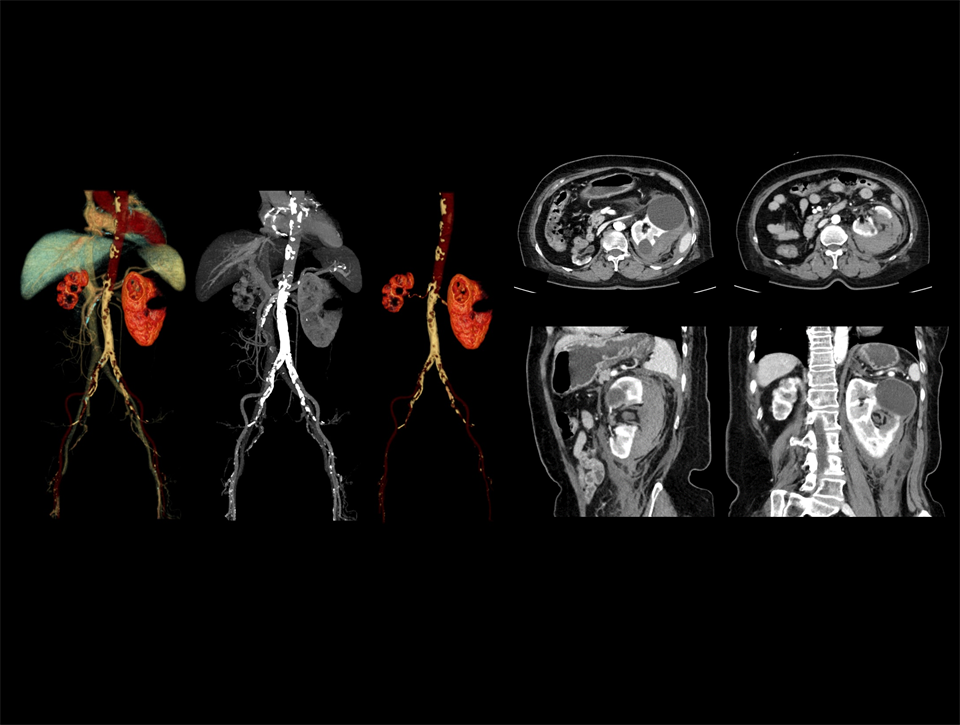

Extracția automată și precisă a vaselor sanguine în CTA carotidian, cu afișarea clară a detaliilor vasculare.

Prin combinarea fluxului de lucru AI cu un tub performant, se îmbunătățește imagistica de urgență în cazurile de traumatisme severe, precum ruptura de rinichi.

CT spectral pentru evaluarea calculilor renali mici.